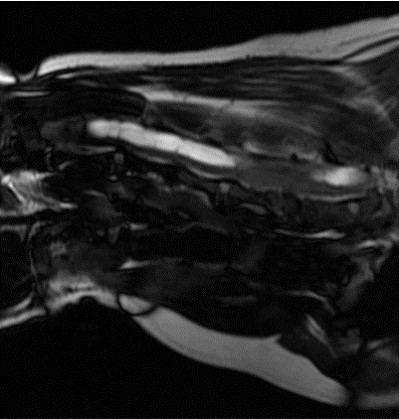

MRI의 경우 특히 뇌와 척수의 신경계와 같은 연부조직의 영상화에 특화되어 있어 다른 영상 기법보다 뛰어난 해상도를 나타냅니다.

- 디스크 질환

- 척수 질환

- 척추 골절

디스크질환 -